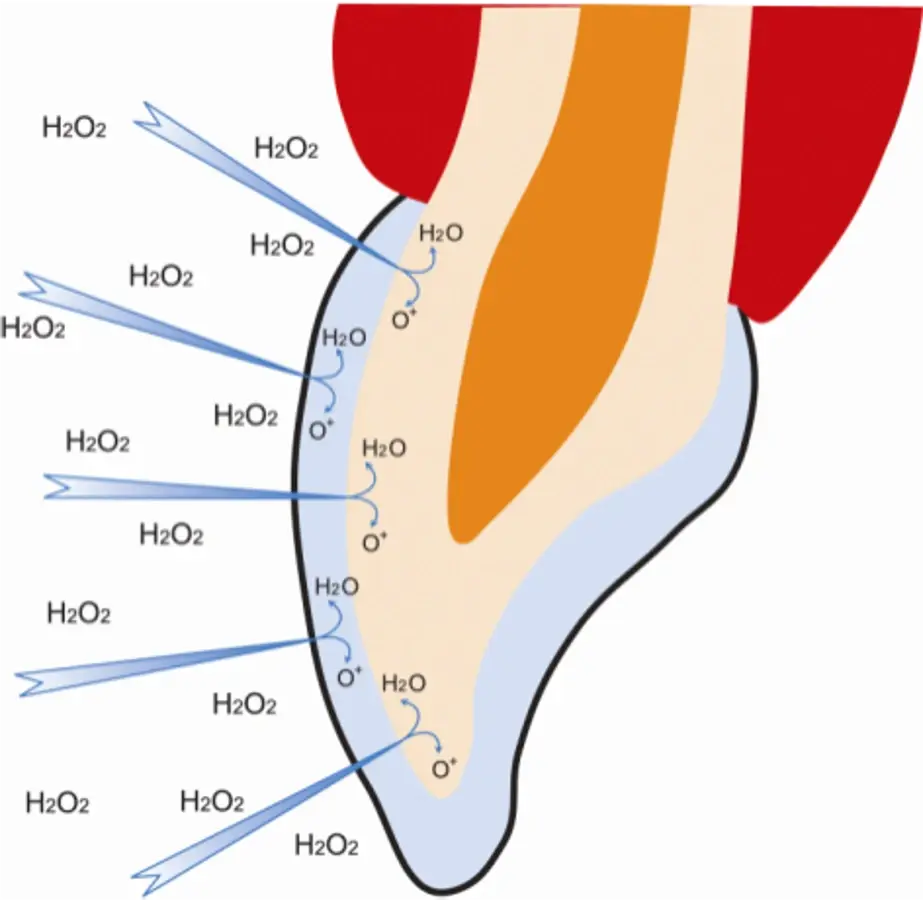

Después de eso, uno de los mayores fabricantes lanzó TresWhite Ortho, un aclarador especial para pacientes con ortodoncia fija. Para poner las cosas en contexto, es importante saber que el peróxido de hidrógeno tiene un bajo peso molecular de 32 mg/m, lo que permite su fácil dispersión a través del esmalte hacia la dentina5. Una vez alcanza la dentina, las moléculas de oxígeno actúan sobre los pigmentos oscuros rotándolos y fragmentándolos, creando así un efecto de aclaramiento de la estructura dental. El peróxido de hidrógeno actúa de manera polidireccional dentro de los dientes, aún en zonas cubiertas por aditamentos como brackets, lo que hace posible que se logren aclaramientos en las áreas situadas debajo de estos aditamentos6,7.